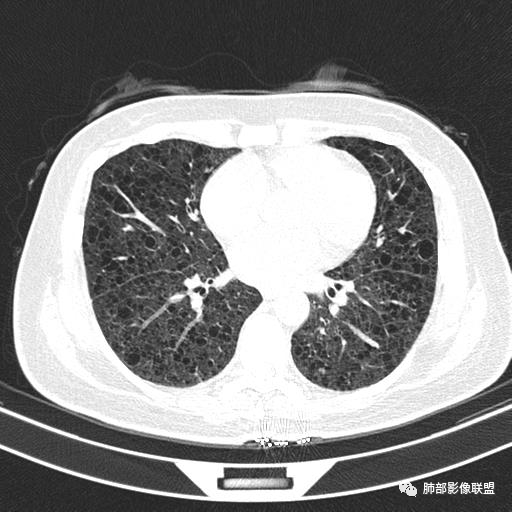

双肺弥漫囊腔,累及肋膈角,囊腔形态相对规则单一。

CT平扫示双肺弥漫分布大小不等囊状薄壁透光区,无内、中、外带分布差异,间质稍示增厚。拟LAM

女,46,活动性气喘1年。苯吸入史半年。胸部CT:两肺弥漫囊腔,上至肺尖,下至肋膈角,形态类似小囊腔。考虑:LAM,鉴别LIP,BHD,PLCH等。

双肺弥漫大小不一薄壁含气囊腔,囊间肺组织正常,正常肺背景,肺尖肺底受累;青年女性,气喘,支持LAM

双肺多发大小相近的囊状影,分布趋势趋于一致,中年女性,考虑LAM。部分囊内见血管及分隔影,小叶中心性肺气肿代排

CT表现:双肺弥漫大小不等的薄壁囊腔,囊壁<2mm,外形规则,血管影多位于囊腔周围,囊腔之间肺组织正常,随着疾病进展到晚期,囊腔变大、增多,不可胜数,囊腔可融合成较大的囊,与肺气肿相似,形成间质性肺纤维化。部分病例可出现结节影。